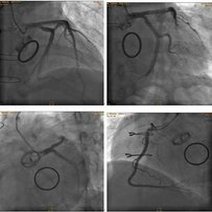

- 冠状动影怎么做一、冠状动影怎么做二、冠状动术前准备三、冠状动影注意事冠状动影怎么做1、冠状动影怎么做冠影检查是目前唯一直接察冠状动形态的方法,号称冠心病断的标准

- 冠状动脉造影手术过程,一,冠脉造影的适应症冠脉造影的主要目的是明确有无冠状动脉疾病,选择治疗方案和判断预后,有心绞痛症状的患者,尤其是药物治疗无效或者通过无创检查发现有高危因素的患者应行冠状动脉造影术,对拟形瓣膜性心脏病或先天性心脏病手术的